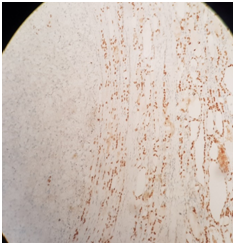

In May 2016, CT thorax abdomen and pelvis for assessment of weight loss revealed no evidence of renal cancer recurrence, but there was a heterogenous right thyroid lobe lesion measuring 2.3cmx1.8cm. Subsequent ultrasound assessment of this thyroid lesion showed a right lobe solid and isoechoic nodule with few cystic areas measuring 3.5x2.74cm. There were other small nodules less than 0.5cm in the left lobe. Fine needle aspiration (FNA) and cytology of the right lobe nodule in June 2016 was suboptimal, repeat FNA and cytology around 2weeks later was of borderline adequacy and the findings were non-specific. He proceeded for total thyroidectomy in July 2016, the histology revealed clear cell neoplasm with morphic features in keeping with metastatic renal cell carcinoma (Figure 1&2). Immuno- histochemical stain showed that the tumor was negative for thyroid transcription factor -1 (TTF-1) (Figure 3) and positive for CD10 (Figure 4). He was commenced on thyroid hormone replacement following thyroidectomy. Postoperative staging with positron emission tomography (PET) scan was unremarkable.6

Figure 1&2 Show the interface between normal thyroid tissue and the tumor.

Figure 4 Immunohistochemical stain; CD10 is positive in metastatic renal cell carcinoma and negative in follicular proliferation.